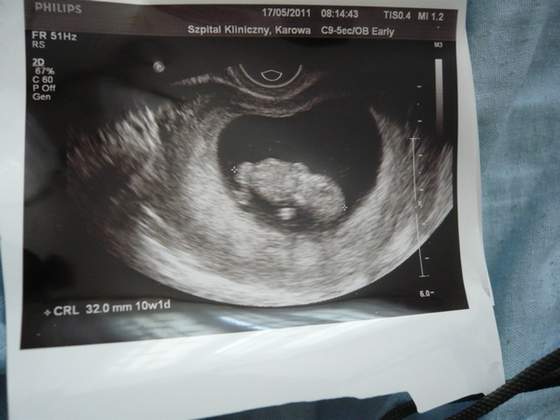

uderzen 156/'min wiec szybciutko puka:-)jesli chodzi o toxo to Gin mi powiedzial ze na 90% zarazilam sie 20tygodni temu czyli przed zapłodnieniem.Ale dla świetego spokoju zrobilam sobie dzis powtórke z badan. Za 2 tyg mam wizyte i bedzie juz przez brzuszek:-)beda badania na przezierność karkowa i choroby genetyczne.Jedna rzecz mnie wkurzyla nie dał mi L4

powiedzial ze jest zbyt wczesna ciaza i pomyślimy za 2 tyg

Wklejam usg mojej kluski;-)